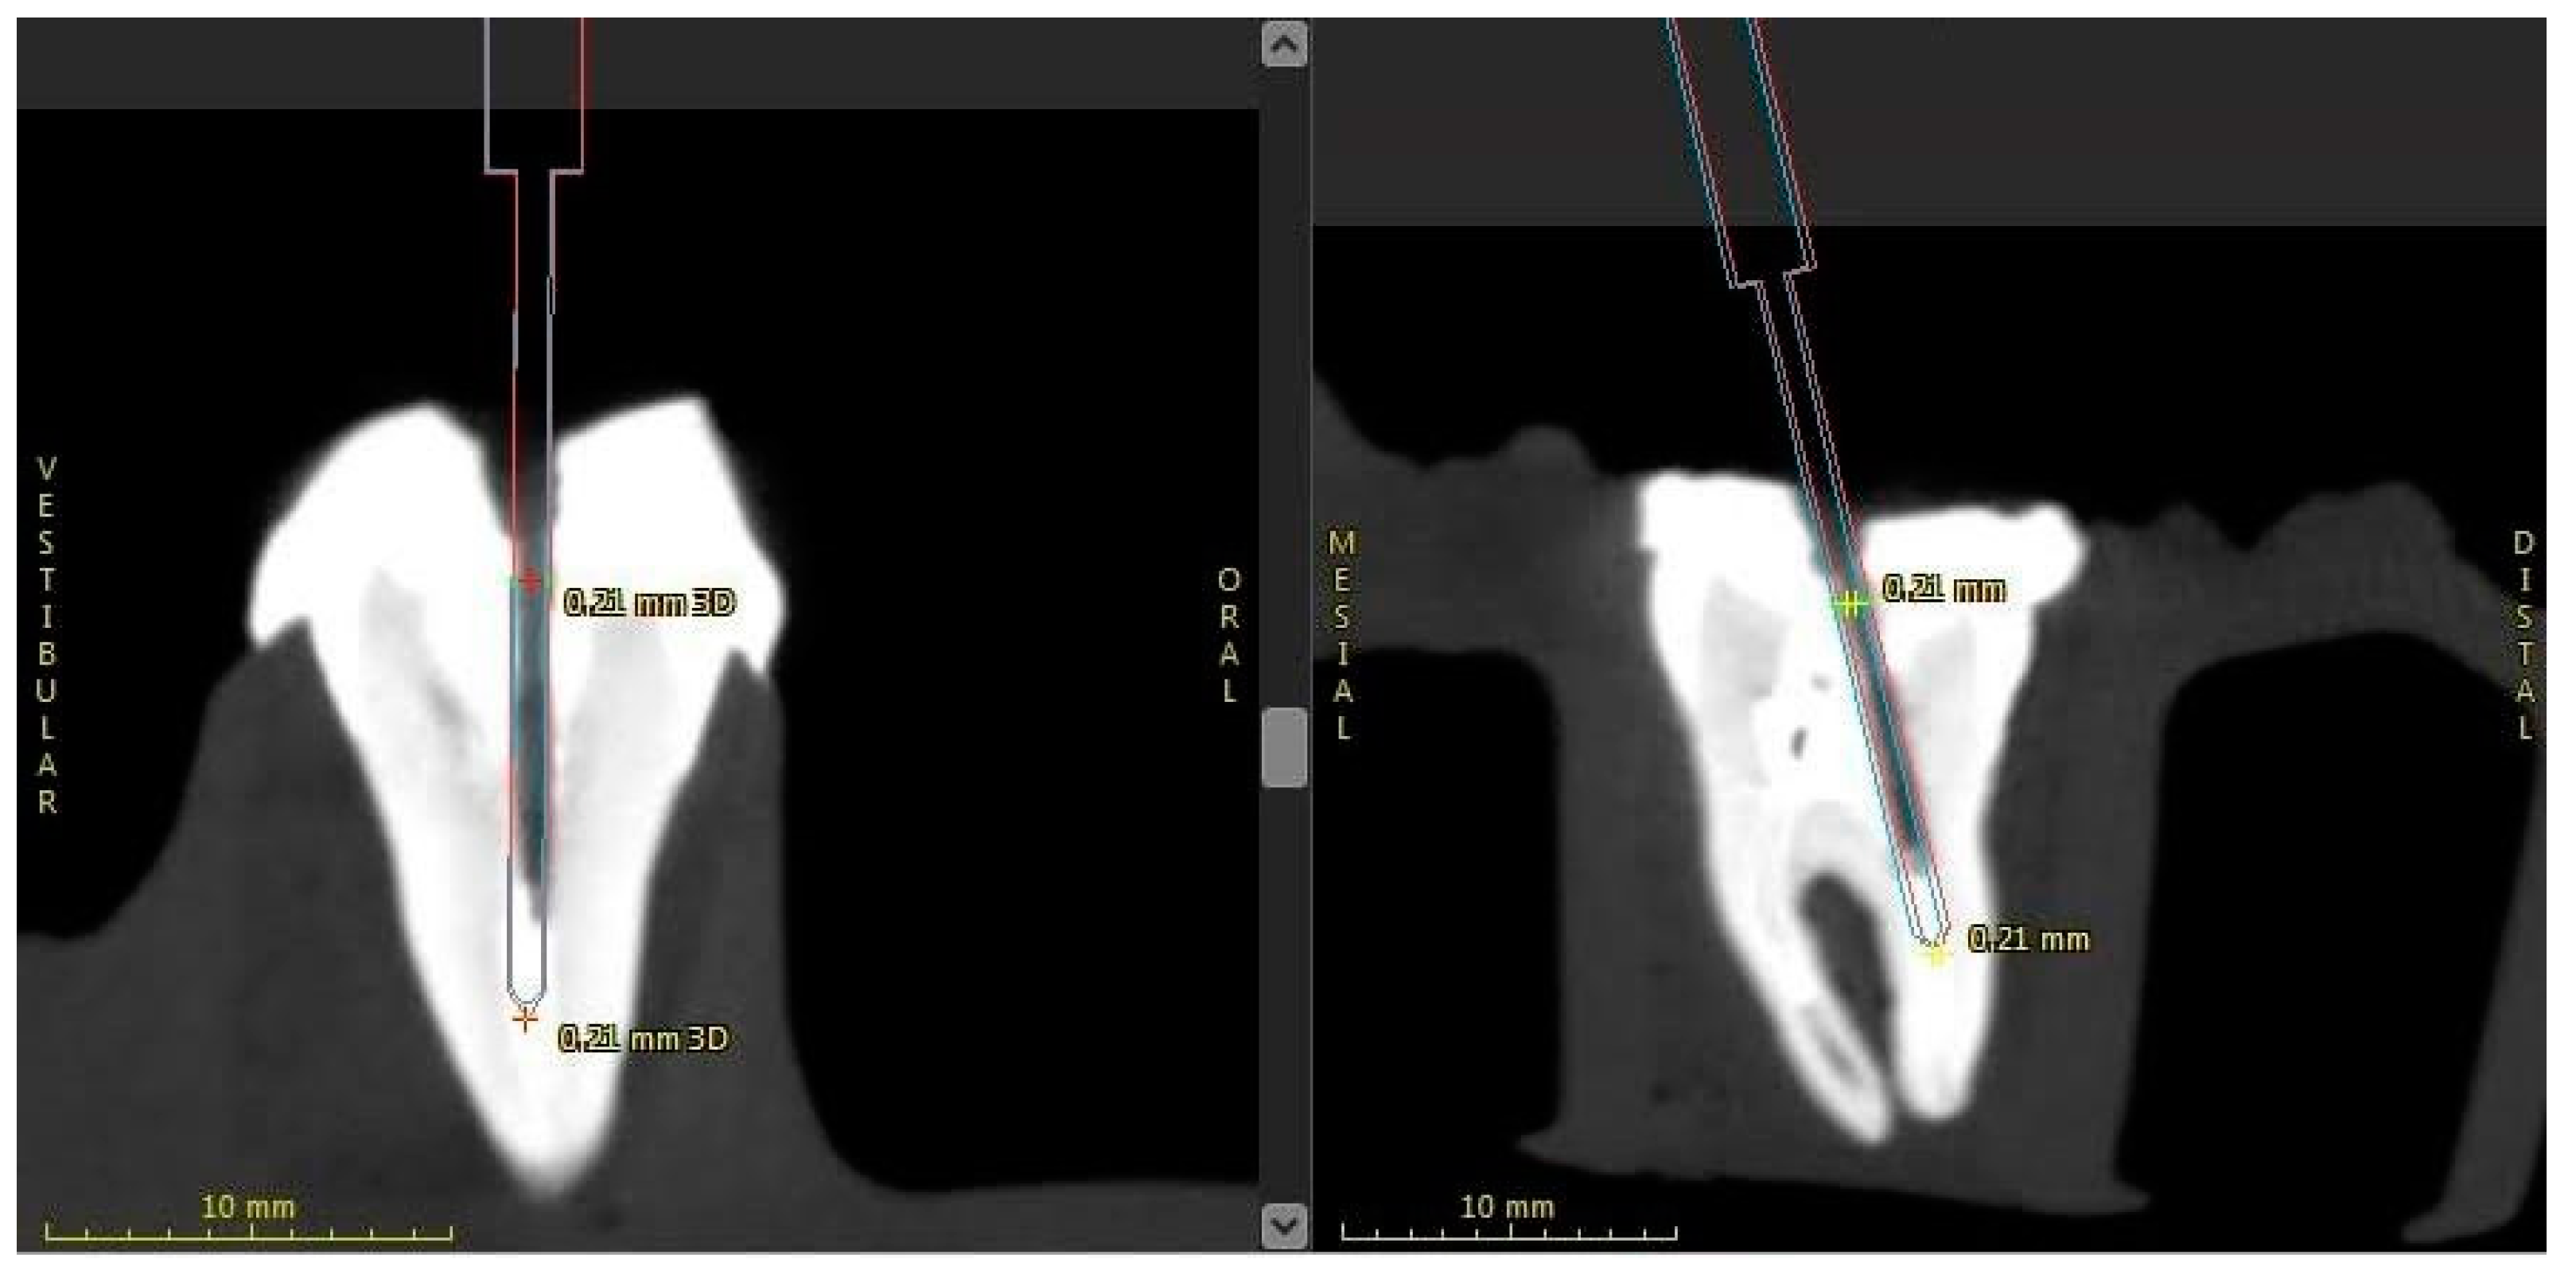

2.6. Evaluation of Accuracy